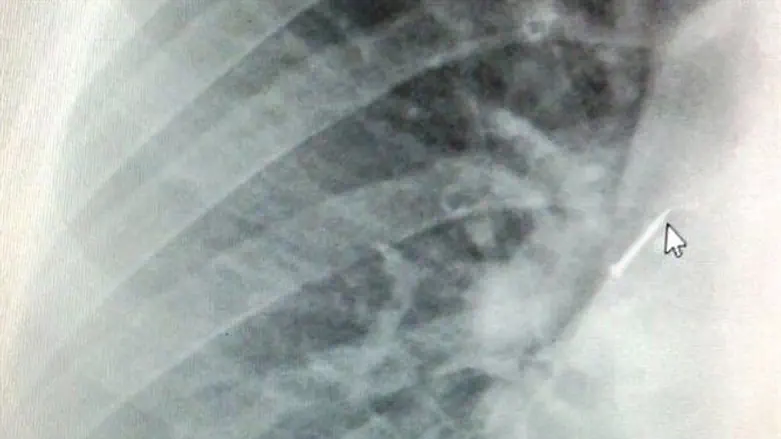

ד"ר ליאוניד ליפשיץ, רופא בכיר במחלקת אף אוזן גרון, סיפר, "לילד נערכו בדיקות מקיפות וצילומי הדמיה שהראו, כי הנעץ חדר דרך קנה הנשימה לתוך הסימפון, ממש בכניסה לריאה. הילד הורדם בהרדמה כללית והוכנס לחדר הניתוח, שם הכנסנו לקנה הנשימה שלו צינור גמיש (ברונכוסקופ) שבתוכו סיב אופטי ותופסן, ושלפנו בהצלחה נעץ בגודל של סנטימטר עם ראש פלסטיק גדול"